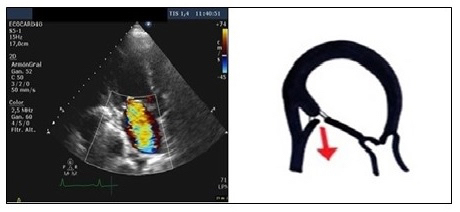

In the asymmetric closure pattern of IMR, a “hockey stick” or seagull sign is shown on the echocardiogram. The anterior leaflet in systole is below the posterior, which is also stressed, altering the coaptation. An eccentric jet of insufficiency appears, ipsilateral to the posterior leaflet, which goes to the posterior region of the left atrium (LA) (Figure 1). This pattern is typical of inferior or inferolateral infarction.

Figure 1. An apical four-chamber view, showing ischaemic mitral regurgitation with asymmetric closure: the anterior leaflet in systole is below the posterior, also stressed, altering the coaptation. The insufficiency jet is eccentric, ipsilateral to the posterior leaflet and is directed towards the posterior region of the left atrium. Echocardiographic image on the left and schematic drawing on the right.

Ao: aorta; LA: left atrium; LV: left ventricle